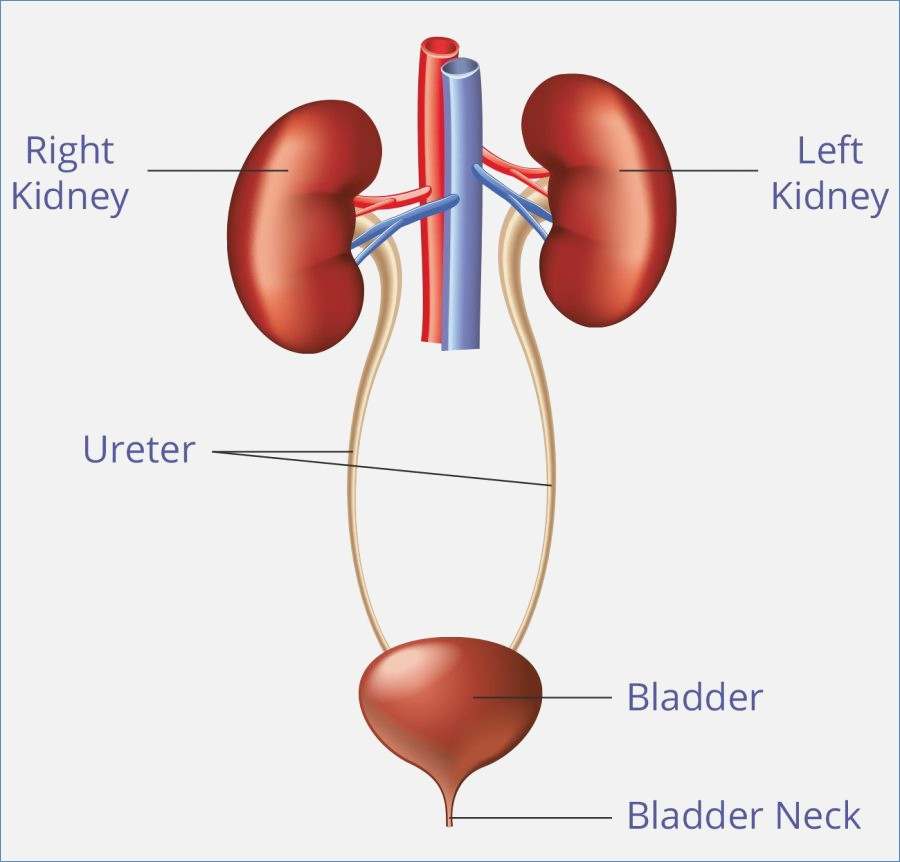

location of the bladder in the human body

Posts: location of the bladder in the human body